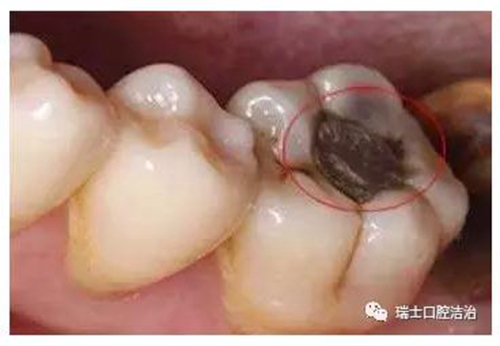

齲齒對兒童牙齒的損害不容忽視,國際上已經(jīng)將齲齒、腫瘤以及心血管疾病列為危害人類健康的三大疾病。齲齒是牙齒在多種因素影響下,牙硬組織脫礦、有機質(zhì)溶解、牙組織進行性破壞,導致牙齒缺損的常見疾病。

2.jpg

兒童作為預防齲齒的重點人群,家長必須引起足夠的重視。家長要隨時留意孩子的牙齒情況,尤其是后磨牙,比如孩子的第一顆恒牙六齡齒(下頜)就是很容易發(fā)生齲齒的牙齒。一旦發(fā)現(xiàn)齲齒,就必須及時治療,不要心存僥幸,也不能輕視齲齒的破壞力。齲齒可完全破壞整個牙冠,僅殘留半截壓根暴露在外,黑乎乎的很是嚇人。